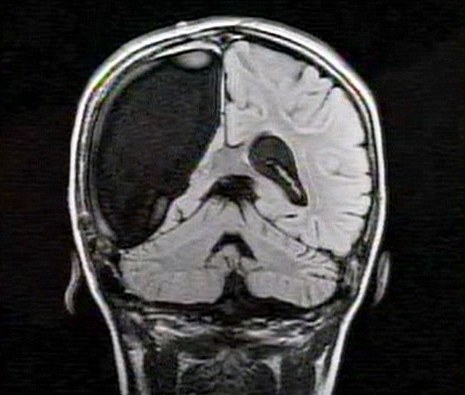

卡梅倫莫特在3歲那年患上一種被稱作大腦功能紊亂“拉斯穆森”綜合癥,這種病癥誘發(fā)患者的無(wú)序暴力行為和嚴(yán)重的癲癇。醫(yī)生建議,治療這種病癥只能通過(guò)嘗試消除引發(fā)此癥狀的大腦組織。而手術(shù)讓莫特失去了幾乎整個(gè)半邊的大腦。

據(jù)悉,莫特在手術(shù)后已經(jīng)可以跑動(dòng)和玩耍,她在術(shù)后的第四周離開(kāi)了醫(yī)院。醫(yī)生表示,雖然右半邊大腦的切除可能會(huì)給莫特帶來(lái)半身不遂的風(fēng)險(xiǎn),但孩子剩余的大腦仍具有很強(qiáng)的重組和布線能力。